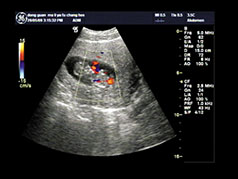

彩超检查

彩超检查?【呼和浩特友谊医院】呼和浩特友谊医院妇科医师介绍说:彩超是目前的彩色超声仪器,它可有效的诊断胎儿是否存在先天性畸形,精准率高达99.99%。对于效果这么好的彩超,很多孕妈咪还不了解它的具体费用是多少。那么,呼和浩特做彩超检查的费用是多少呢?

四维彩超检查费用 友谊医院五月优惠套餐来了,详情咨询医师,网上预约优惠。四维彩超检查的价格每个地方是不一样的,因为每个地方的收费标准存在差异,所以四维彩超的价格是不可以一概而论的,但是建议广大孕妈妈们还是到正规医院做四维彩超,因为正规的医院收费都是标准的。